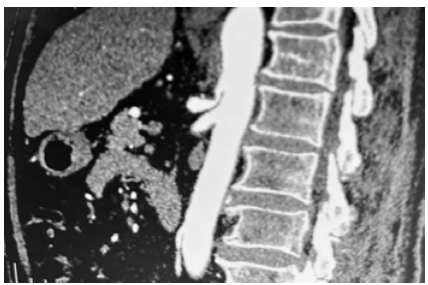

Uma paciente de 48 anos de idade compareceu

ao pronto atendimento com dor abdominal epigástrica,

que piorou no período pós-prandial, há aproximadamente

12 meses. Ela relatou ter procurado atendimento por

múltiplas vezes, sem elucidação adequada do quadro. Já

foi realizada a colecistectomia, sem indícios de melhora.

Houve perda de 10 kg nos últimos 3 meses devido a esse

quadro. Relatou piora da dor nos últimos dias, o que a fez

procurar o atendimento de urgência. A paciente estava em

bom estado, lactato 0,9. Exames cardiológicos estavam

normais. Foi realizada angiotomografia, que evidenciou a

imagem a seguir.

Com base nessa situação hipotética e na imagem acima, assinale a alternativa que apresenta o diagnóstico e a conduta adequados para o caso.